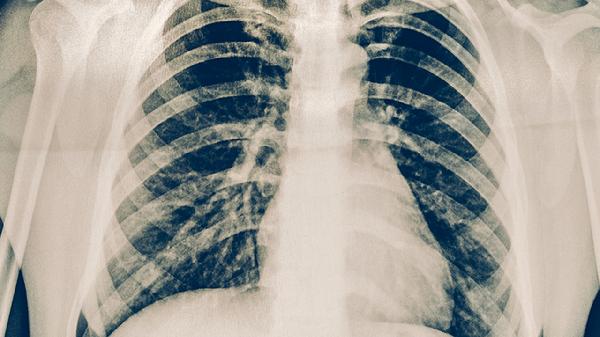

結(jié)核菌素試驗和胸部X線檢查是篩查結(jié)核感染的主要手段。與肺結(jié)核患者密切接觸者、免疫力低下者應每6-12個月進行篩查。發(fā)現(xiàn)結(jié)核感染但未發(fā)病者,可在醫(yī)生指導下進行預防性治療,常用藥物包括異煙肼片、利福平膠囊等。